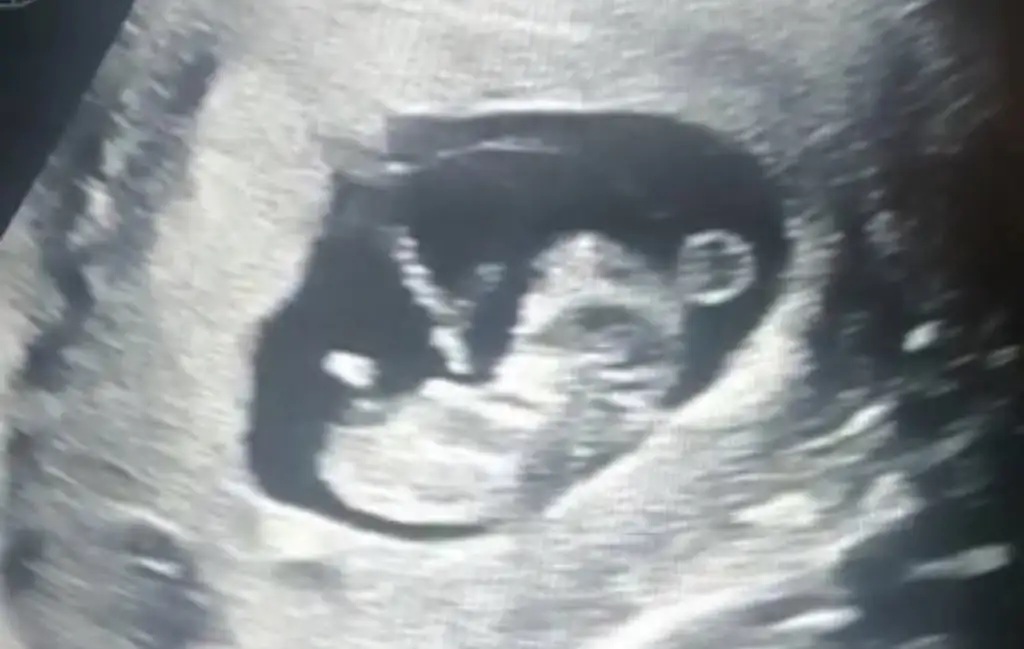

Kızlarrrrrrrrr çok şükür ikili testim temiz çıktı. 10 binde 1 dedi çok çok düşük dedi çok şükür. Cinsiyeti yüzde 80 oranıyla söyledi kağıda yazdırdım akşam size söylicem 😂❤️